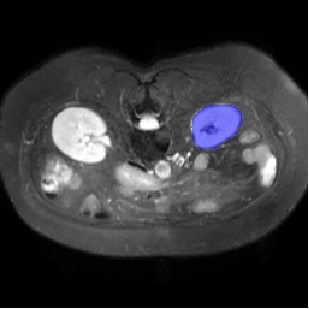

For CMR dataset, we only consider setting 1 because setting 2 is difficult to implement. The results are shown in Table 1 and Figure 4. In general, our proposed method is superior than others. For CHAOS dataset, we consider both setting 1 and setting 2. From the results, we can see the performance of our proposed model is higher than others on CHAOS and CMR datasets. Compared with Q-Net, our mean dice score on CHAOS dataset achieves about 82%. The segmentation results of the model are shown in Figure 5. In setting 2, the slices of the objects containing the test classes are all removed at training stage, and our model still performs well. As can be seen from the Table 2, the segmentation effect of the model on the right kidney is slightly worse than that of ALPNet, but overall, we achieve the best performance. The specific segmentation results are shown in Figure 6. As can be seen from the figure, other methods have excessive segmentation, but ours does not. Our segmentation results are more accurate and reduce redundant segmentation.